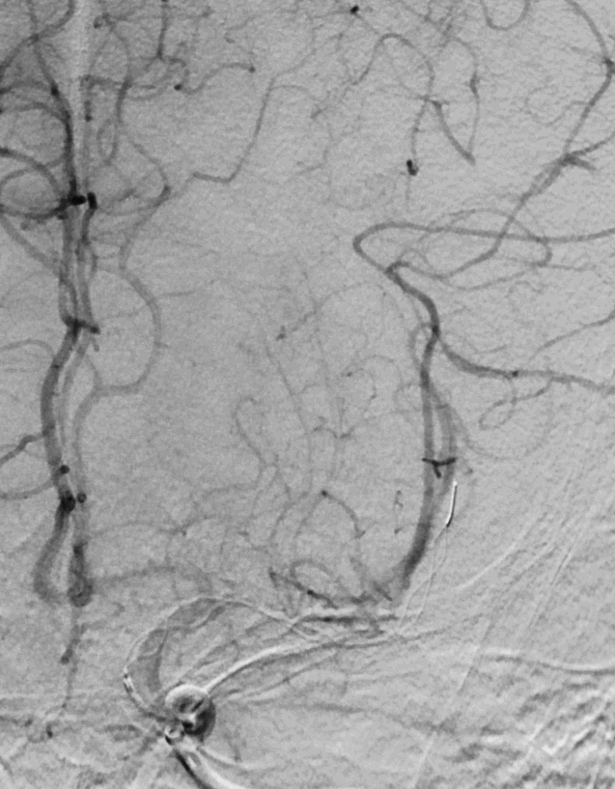

取栓后复查造影见左侧大脑中动脉仍闭塞。

再次将4.0*30mm Syphonet®取栓支架释放到位并造影,见左侧大脑中动脉狭窄段仍明显,且靠近豆纹动脉处。

考虑狭窄明显并夹层形成,遂行4.5*22mm 自膨式闭环支架于左侧大脑中动脉水平段并造影。

最后路径手推造影,造影确认脑血流完全恢复,mTICI 3级。